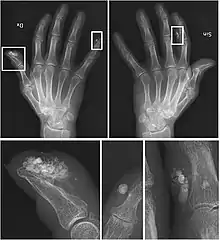

CREST syndrome (calcinosis and sclerodactyly)

X-rays showing calcinosis in a woman with CREST syndrome

Calcinosis

CREST causes thickening and tightening of the skin with deposition of calcific nodules ("calcinosis").